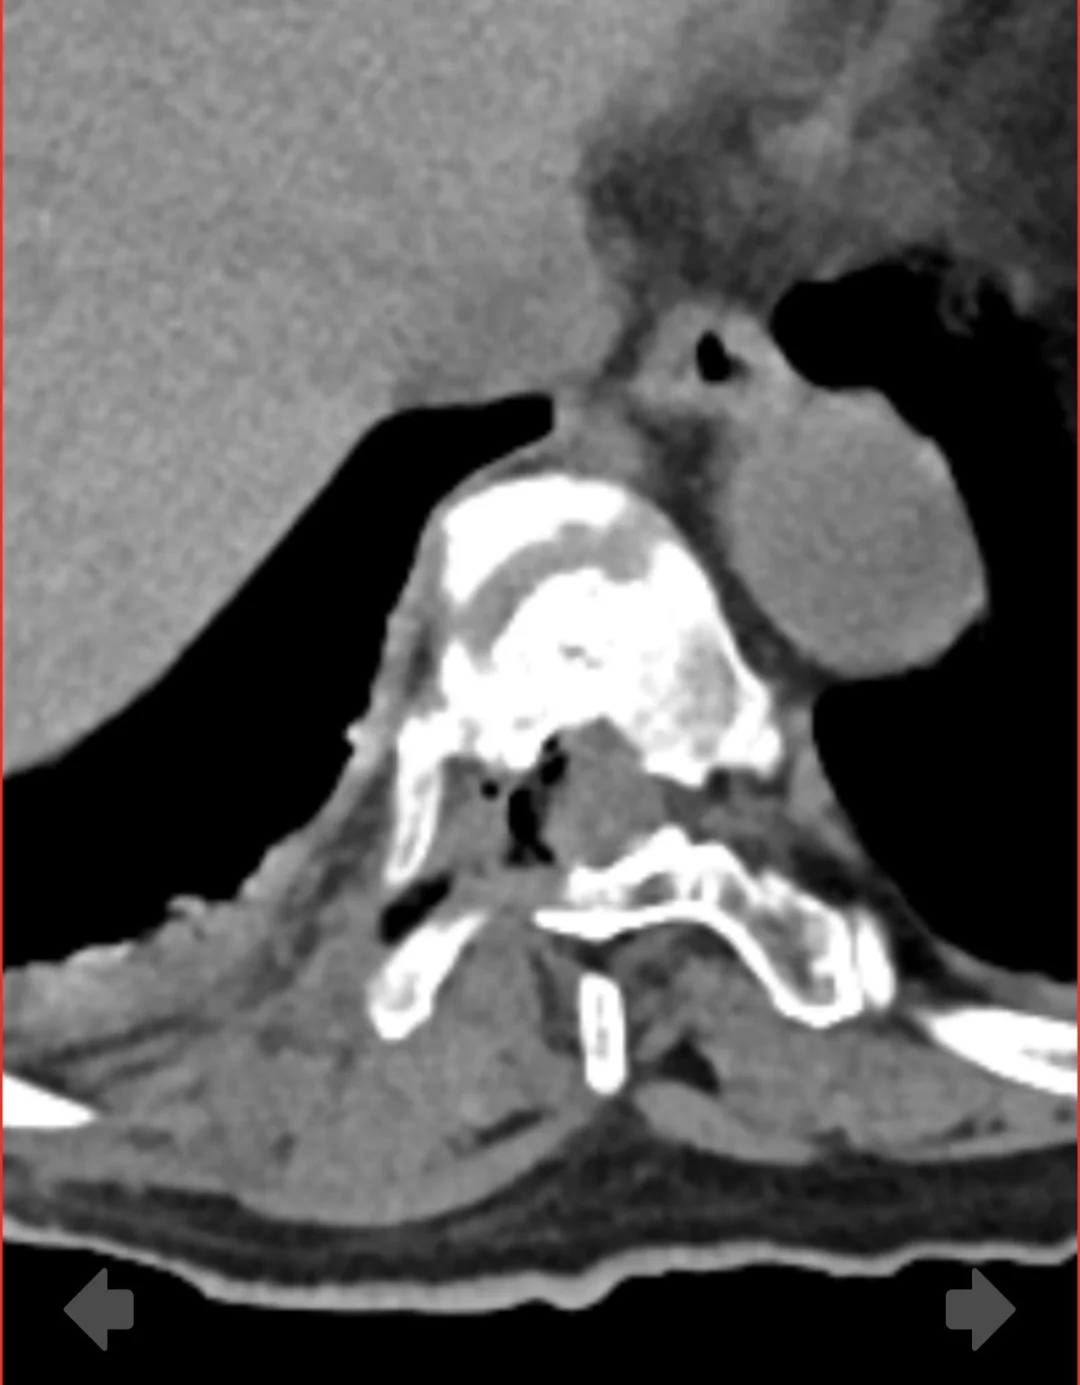

这是我用内窥镜(椎间孔镜)局麻微创做的最严重的胸椎椎管狭窄。胸椎间盘突出 合并胸椎后纵韧带骨化!这种瘫痪风险几乎100%。 奇迹是局麻微创内窥镜术中和术后没有瘫痪[微笑R]很多人不懂胸椎狭窄或者胸椎突出 很多都可以微创解决!安全性也相对高!